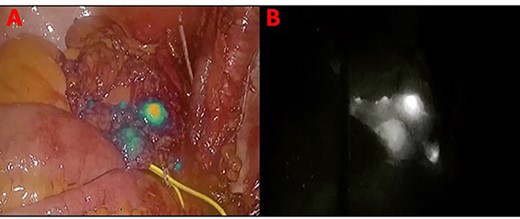

In November 2020, for a diagnosis of prostate cancer at prostatic biopsy, we intraoperatively performed ICG fluorescence-guided lymphography during a laparoscopic radical prostatectomy with pelvic lymphadenectomy. ICG was injected in the prostatic tissue of the patient transrectally through ultrasound identification of the gland. A fine needle was used connected to a 10 cc syringe, taking care to aspirate before injecting the tracer in order to avoid blood vessels. A dedicated laparoscopic high-definition camera system, provided by Karl Storz, was used in our case. This system allowed the surgeon to easily switch from White Light (WL) mode to ICG mode. For this reason, it was very simple to compare WL and ICG mode images. Furthermore, this technique is inexpensive, requiring only a small dose of ICG. Therefore, soon after ICG injection, the lymphatic vessels were identified in the pelvic cavity as fluorescent linear structures running side by side to the iliac vessels. Figure 1 shows the fluorescent lymph nodes in the obturator fossa. Then, using the ‘intensity map’ function (also called ‘overlay function’), lymph nodes can be seen as white structures as this function uses WL (instead of blue light) and eliminates the colors, as shown in Fig. 2. Surgical dissection was therefore performed, avoiding iatrogenic damage to major lymphatic structures. On histological examination, the prostate gland was found to be affected by an acinar adenocarcinoma (with Gleason Score 8, 4 + 4) involving ~20% of the right lobe and 35% of the left lobe. Twenty-four lymph nodes sent as obturators (15 on the right and 9 on the left side) and 10 lymph nodes sent as external iliacs (6 on the right and 4 on the left side) were free from metastases. The patient was discharged 5 days after surgery, and 6 months after surgery, he did not show any complications related to lymph node dissection.

Panel (A) shows the lymph nodes in green color when the blue light is used. Panel (B) shows the lymph nodes in white when the ‘overlay’ function is used.